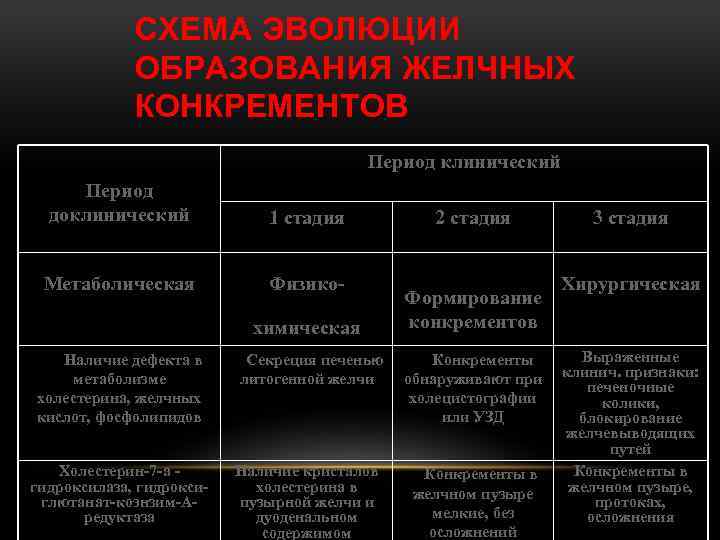

СХЕМА ЭВОЛЮЦИИ ОБРАЗОВАНИЯ ЖЕЛЧНЫХ КОНКРЕМЕНТОВ Период клинический Период доклинический 1 стадия Метаболическая Физикохимическая Наличие дефекта в метаболизме холестерина, желчных кислот, фосфолипидов Холестерин-7 -a гидроксилаза, гидроксиглютанат-коэнзим-Аредуктаза 2 стадия Формирование конкрементов Секреция печенью литогенной желчи Конкременты обнаруживают при холецистографии или УЗД Наличие кристалов холестерина в пузырной желчи и дуоденальном содержимом Конкременты в желчном пузыре мелкие, без осложнений 3 стадия Хирургическая Выраженные клинич. признаки: печеночные колики, блокирование желчевыводящих путей Конкременты в желчном пузыре, протоках, осложнения

СХЕМА ЭВОЛЮЦИИ ОБРАЗОВАНИЯ ЖЕЛЧНЫХ КОНКРЕМЕНТОВ Период клинический Период доклинический 1 стадия Метаболическая Физикохимическая Наличие дефекта в метаболизме холестерина, желчных кислот, фосфолипидов Холестерин-7 -a гидроксилаза, гидроксиглютанат-коэнзим-Аредуктаза 2 стадия Формирование конкрементов Секреция печенью литогенной желчи Конкременты обнаруживают при холецистографии или УЗД Наличие кристалов холестерина в пузырной желчи и дуоденальном содержимом Конкременты в желчном пузыре мелкие, без осложнений 3 стадия Хирургическая Выраженные клинич. признаки: печеночные колики, блокирование желчевыводящих путей Конкременты в желчном пузыре, протоках, осложнения